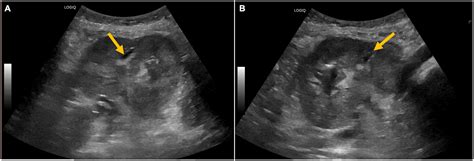

• Imaging Studies: Imaging tests such as ultrasound, CT scan, or MRI can provide detailed images of the kidney and help locate the abscess.

Imaging studies are particularly important as they can confirm the presence of an abscess and guide the treatment plan.

• Percutaneous Drainage: This minimally invasive procedure involves inserting a needle or catheter into the abscess to drain the pus. It is often guided by imaging techniques such as ultrasound or CT scan.